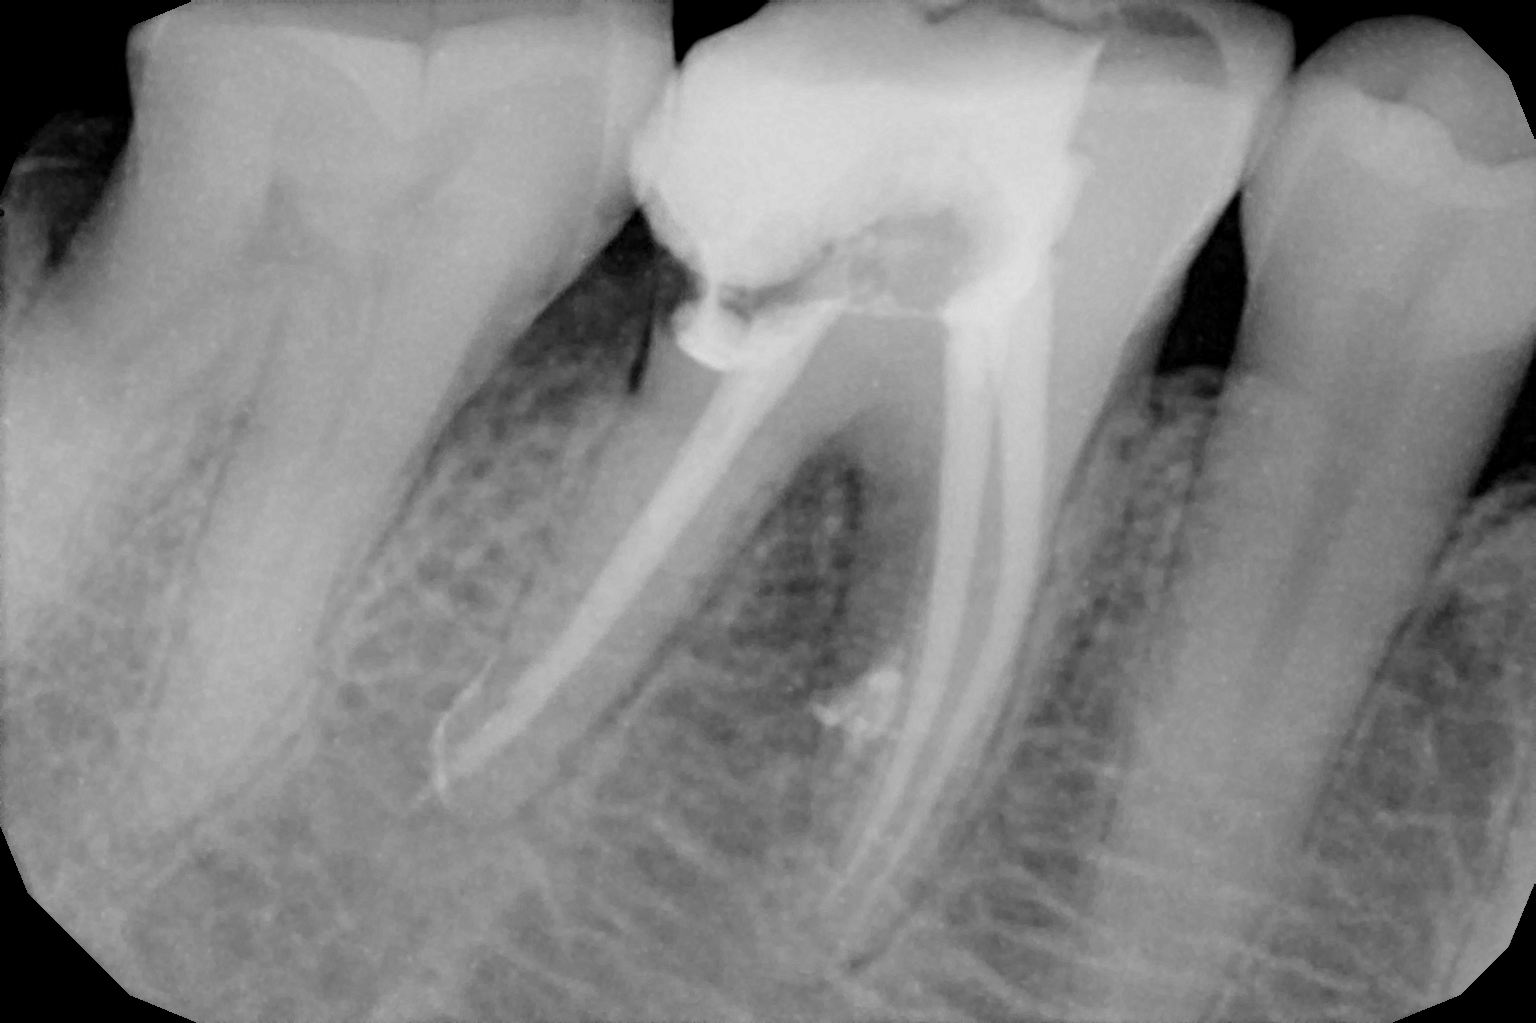

When the tooth is is sensitive to particularly hot and cold. When you cannot chew from that side or there is associated action of pain and swelling with same tooth, root canal treatment can save the tooth. For root canal treatment our clinic is equipped with state-of-the-art facility. We are following the protocol that is universally accepted and considered as a gold standard We are using rubber Dam for maximum possible cases. The root canal treatment is done under local anaesthesia that's why mostly it is painless . The rubber Dam isolation helps in proper irrigation and it provides much needed ease to the operating dental surgeon and the patient . The sealer and filling material are one of the Prime requisite of quality root canal treatment, it needs use of multiple X rays to really judge whether the results are acceptable or not. In older days root canal was just about cleaning the decade portion, removing the Pulp and filling it with biocompatible material but nowadays the root canal treatment it is very much advanced the precision is increased manifold. The materials and armamentarium that is required for efficient root canal have advanced in exclusion initial ways the the Abstract of all these things is the patients are getting great results after root canal treatment. Only the root canal is not sufficient to make a tooth functional again ,it needs use of Core buildup material and complete coverage Crowns according to the tooth position. During Covid19 time we have studied and implemented use of of high strength composites in our practice and the results of it are amazing many times it has saved tooth from being restored with crown. In some cases where the tooth is grossly carious we need a complete coverage crown. The materials and the Crown materials are are available in various price ranges. We prefer only the best of materials for our patients. We believe that to perform best treatment we need best of the armamentarium and best of the material for our patients who value and deserve the best of the treatment.